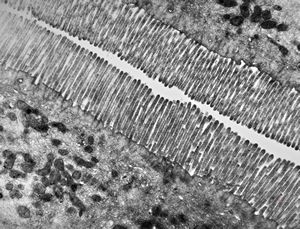

normal mucosa - jejunum - microvilli(anchored core rootlets)

normal mucosa - jejunum - microvilli

enterocyte - normal and celiacal microvilli